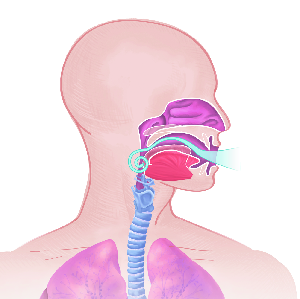

Über 860 Stichworte mit 120 Illustrationen auf 400 Seiten machen aus dem Lexikon der Lunge ein

wertvolles Werk.

Detailreiche Fotografien aus der medizinischen Praxis ergänzen die Texte; moderne, genaue,

wissenschaftliche Zeichnungen geben Einblick in die Anatomie und die Funktion der Lunge und

anderer Organe.